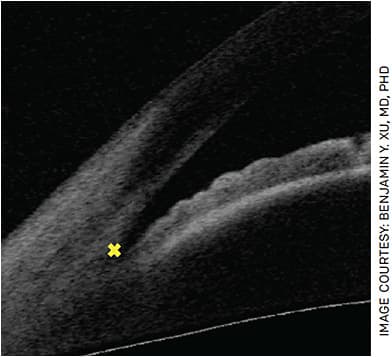

The scleral spur is a key anatomical landmark that must be identified in AS-OCT images to obtain measurements of important biometric parameters in angle closure (Figure 1). Unfortunately, scleral spur detection is an expertise-dependent and time-consuming task that requires manual labeling. However, DL algorithms that provide expert-level detection of the scleral spur in AS-OCT scans have recently been developed, which could greatly enhance the clinical utility of AS-OCT.15